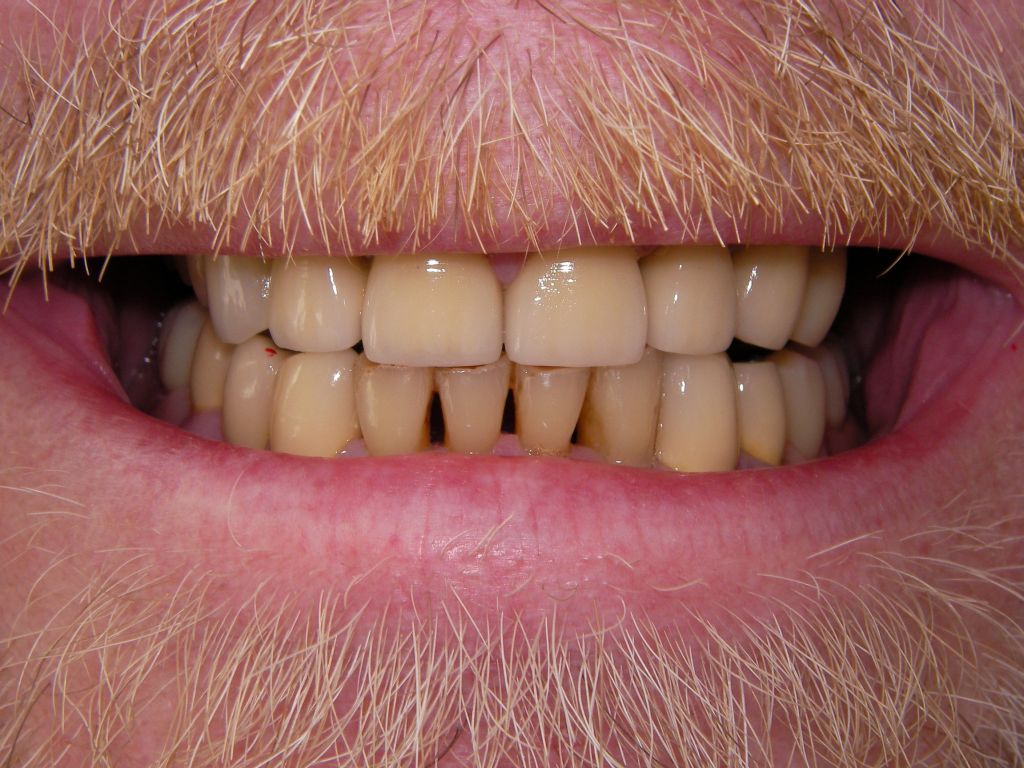

Hier das vorläufig letzte Bild dieses Falles mit maximaler Lippenöffnung einige Tage nach Eingliederung von Kronen und Prothesen bei der Nachkontrolle (Ende März 2006). Bislang lief, von einigen anfänglichen Prothesendruckstellen abgesehen, die aber leicht behoben werden konnten, alles glatt. Die Heiß-/Kaltempfindlichkeiten an den beschliffenen Zähnen, die häufig auftreten, waren nach der Zementierung der Kronen verschwunden. Die eigentliche prothetische Behandlung dauerte vom 22.2.06 bis zum 20.3.2006 (nur 5 Sitzungen), also 4 Wochen und war damit recht zügig. Ähnliche Fälle können auch 6 Wochen dauern. |